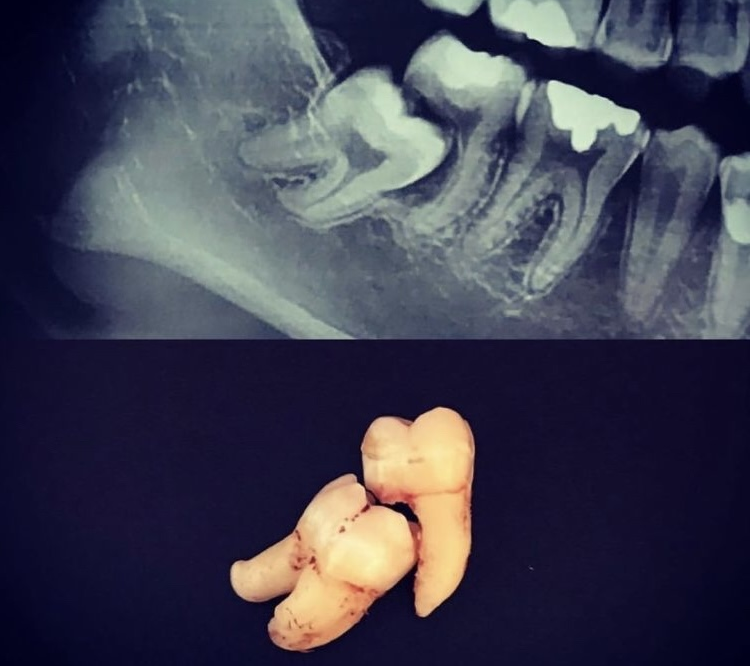

异位智齿与邻牙间的缝隙也是刷牙和牙线难以清洁到的卫生死角,长期食物嵌塞和不良的口腔卫生状况极易导致智齿和邻牙的龋坏,引发牙髓和根尖炎症;除此之外,智齿长期慢性的“推挤”作用还会导致邻牙牙根吸收、牙齿咬合紊乱等并发症。

(智齿引起邻牙牙根严重吸收,最终两牙双双被拔除)